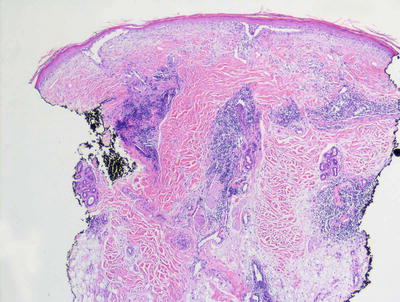

Lichen aureus demonstrates a lichenoid inflammatory infiltrate along the epidermal junction, usually characterized by little destruction of the epidermal basal layer, similar to the histologic changes that have been described in adults with the same condition [33] (Figs. 4.8 and 4.9). The epidermis is unremarkable except for focal basal vacuolization and exocytosis of lymphocytes. Within the dermis, there is a dense lymphohistiocytic infiltrate usually confined to the papillary dermis [35]. The distinguishing diagnostic feature is the presence of erythrocyte extravasation with hemosiderin deposition, often accumulating within dermal macrophages. The gold brown pigment may be readily apparent on routine histologic sections, but can be better visualized on iron stains.

Fig. 4.8

Lichen aureus demonstrates a band-like infiltrate along the papillary dermis with focal hemorrhage

Fig. 4.9

Papillary dermal hemorrhage and a lymphocytic infiltrate without obvious vascular destruction are features of lichen aureus